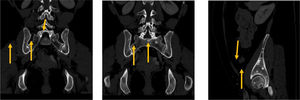

En los cortes pélvicos, se evidenciaron múltiples lesiones escleróticas (ya descritas en la TC previa), sin hallazgos de tumor primario. Como hallazgos radiológicos principales se apreciaron múltiples focos escleróticos endomedulares metafisoepifisiarios, con márgenes bien definidos, de distinto número y tamaño (sin llegar a superar el centímetro) acetabulares, ilíacos bilaterales y sacros sin disrupción cortical ni compromiso de partes blandas adyacentes; todos, hallazgos radiológicos no agresivos. Dichas enostosis presentaban agrupación periarticular, encontrándose estables en número y tamaño con respecto a la TC anterior. Los hallazgos sugerían displasia osteoesclerosante, a valorar la osteopoiquilosis. Figura 1.

En la TC, la osteopoiquilosis presenta múltiples focos enostóticos subcentimétricos (5-10mm), simétricos, metafisoepifisiarios en huesos largos, respetando cráneo y esqueleto axial. Por lo general, no suele presentar deformidad o malformación de estructuras óseas y ello genera un debate abierto sobre si resulta del todo apropiado incluirla dentro del grupo de las osteocondrodisplasias, ya que en estas sí es frecuente encontrar deformidad o malformaciones óseas3.